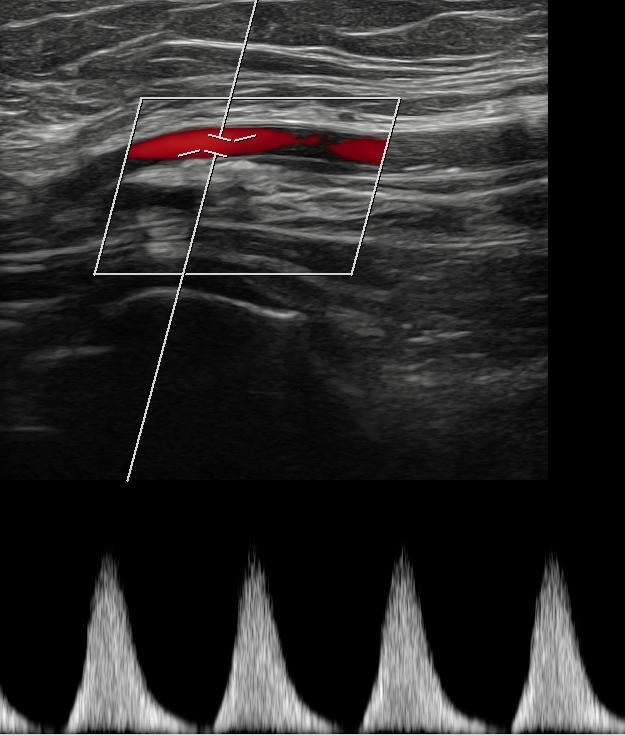

Dado el acceso a ecografía clínica en el centro de salud, se realiza la misma.

Hallazgos ecográficos

Se identifican placas de ateroma en ambas arterias femorales comunes, con pérdida del flujo diastólico, hallazgo sugestivo de enfermedad aterosclerótica significativa.

Los engrosamientos parietales difusos o focales sugieren aterosclerosis. En territorios de alta resistencia, el flujo normal es trifásico: un pico sistólico anterógrado, una corta fase reversa por resistencia periférica y un componente diastólico anterógrado de baja velocidad. El flujo arterial sano es laminar, con velocidades habitualmente menores de 1,5 m/s. Las estenosis hemodinámicamente significativas reducen más del 50% de la luz vascular y producen aliasing en Doppler color, con velocidades superiores a 1,3 m/s. Distalmente a una estenosis grave, los flujos se vuelven monofásicos, variando su resistencia según la vasodilatación distal.